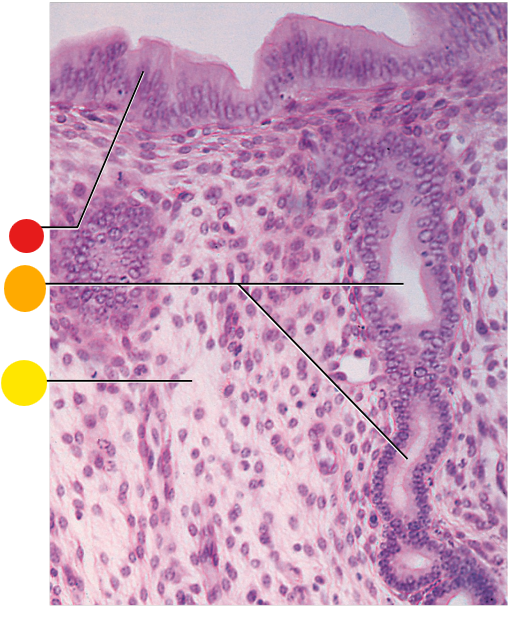

red

endometrium

light green

endometrial glands

orange

myometrium

yellow

perimetrium

red

epithelium

what is this?

uterus wall

red

simple columnar epithelium

orange

endometrial gland

yellow

lamina propria

where will you find endometrial glands?

within the lamina propria of the endometrium

What tissue type lines the endometrial glands

they are invaginations of the simple columnar epithelium

red

simple columnar epithelium

orange

lamina propria

yellow

endometrial glands

where is this?

endometrium of uterus